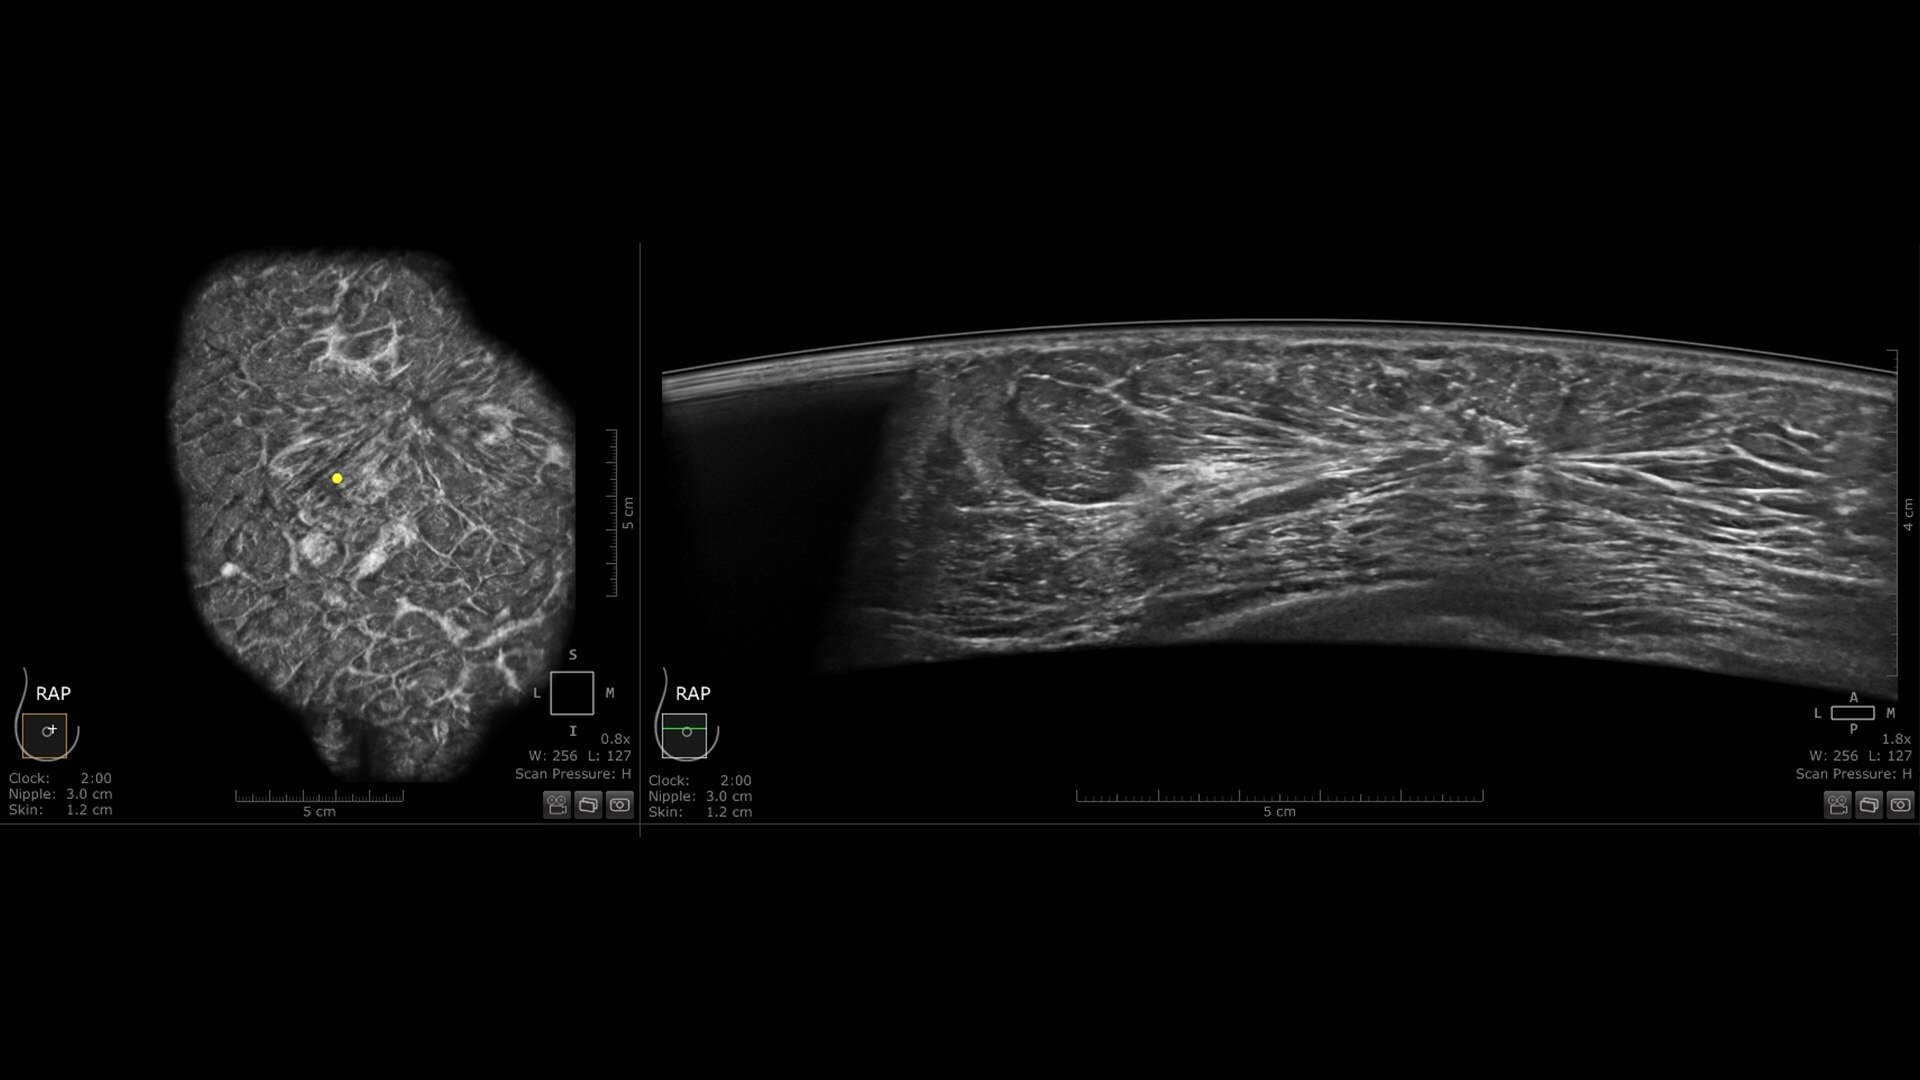

Centralized reading everywhere with the Invenia ABUS Viewer with AI Assistant

Invenia ABUS Viewer’s efficient workflow, with AI Assistant**, allows physicians to quickly review, interpret, and archive exams, even remotely.

• Experience up to 93%⁵ sensitivity for lesion detection and reduce reading time by 33% with QVCAD™⁶

• Decrease benign biopsies by up to 55% with Koios DS™ Breast

s-curve-workflow-desktop-ci-en